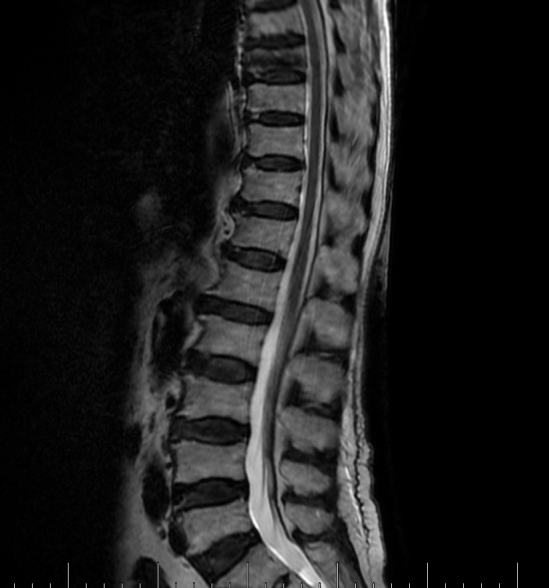

吴老太太今年86岁,同时患有心脏病、老慢支、哮喘、糖尿病等多种疾病,不久前因为并发心衰、呼衰在独墅湖医院经抢救后脱离危险。然而不巧的是,几天前自己在家只轻轻扭了一下腰,就感觉背部疼痛难忍,寝食难安。于是来到我院骨科就诊,医生怀疑是脊柱骨质疏松性骨折,安排收治住院,对病患进行磁共振检查后证实是“第8胸椎压缩性骨折”。

医生在诊断后决定行经皮椎体后突成形术(简称PKP术),需要病人在全身麻醉下俯卧位,医生在全程透视下完成手术。对于一般的患者来说不成问题,而对吴老太太而言却难以实施。首先,她的全身情况较差,心肺功能不全,基础疾病多且严重。入院时就有明显的呼吸困难,氧饱和度只有70%左右,很难耐受全身麻醉。即使勉强度过手术阶段,术后也可能要气管插管,靠呼吸机维持生命,肺部感染则难以控制。其次,如果采用局部麻醉俯卧位手术,尽管可以规避全麻的风险,但该患者根本不能承受俯卧位对心肺功能的影响。但如果不采取手术,卧床以及日夜不停的疼痛对已经遭受过心衰和呼衰的吴老太太来说是雪上加霜。